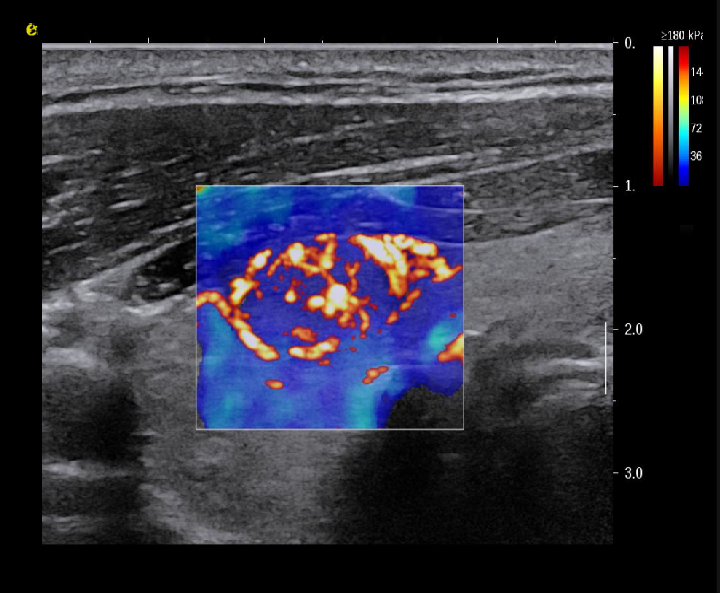

实时剪切波弹性成像

评估组织的软硬,并且提供定量数值,从而提示组织的良恶性。

image.png

恶性占位常常向周边组织进行侵润及扩散,二维很难观察到浸润部分的边界。使用实时剪切波成像能够对占位及周边组织进行硬度评估,通过颜色编码来区分不同组织的硬度信息,直观的观察占位组织的边界信息,更方便区分占位组织和正常组织的边界,准确评估消融范围。

左图病例所示:

钼靶阴性,B型发现非肿块病变

剪切波弹性成像见明确的硬度增高区域。

穿刺及手术病理结果:浸润性导管癌(IDC)

非肿块型病变:B型图像无法确认病变范围,E成像帮助发现异常区域和评估